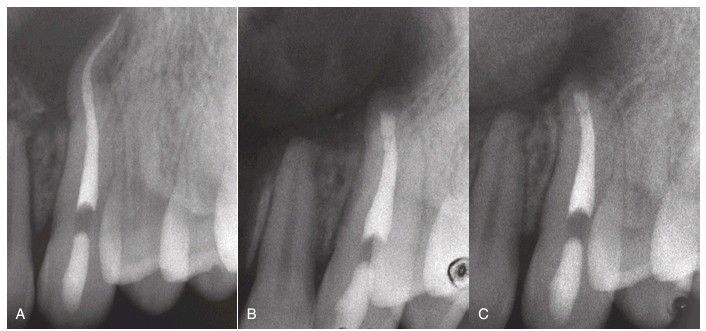

(A) Anatomic problem of a severe root curvature, for which surgery is indicated. (B) Apical resection and root end retrograde mineral trioxide aggregate the seal. (C) An image taken 4 months after surgery shows regeneration of bone.